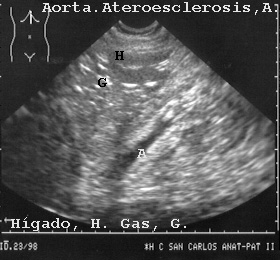

Así por ejemplo en la Fig 22 hay una aorta con importante ateroesclerosis.

22AORTAA.JPG (32163 bytes)

Fig 22